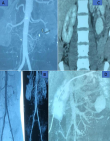

Diagnostic assessment: laboratory tests evaluating renal function and blood film resulted normal. During one of the episodes, the patient had undergone an abdominal ultrasound, which showed a left renal intraparenchymal aneurysm about 16 mm in diameter. Abdominal computed tomography angiography revealed an aneurysm of the left inferior polar segmental artery measuring 42 in height and 32x33 mm in transverse axes. The aneurysm was surrounded by a circumferential hematoma measuring 12.7 mm in thickness (Figure 1).

Figure 1: A, B) abdominal computed tomography angiography revealed an aneurysm of the left inferior polar segmental artery measuring 42 in height and 32x33 mm in transverse axes; (C, D) the aneurysm was surrounded by a circumferential hematoma measuring 12.7 mm in thickness